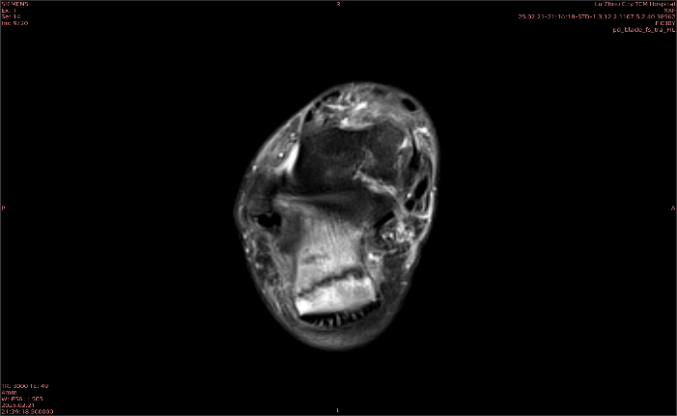

舉例圖像

圖1

專業(yè)解釋看不懂沒關(guān)系,大家看圖1和圖2就可以了,這是同一個(gè)患者跟骨的磁共振和CT圖像,圖1的紅色箭頭指示的黑線就是磁共振圖像顯示的骨折線,一目了然。而對比圖2的CT圖像上并未顯示異常。